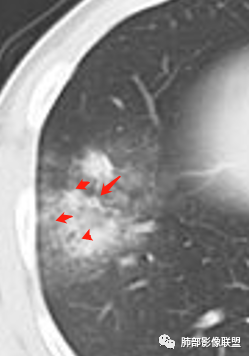

大家再看看周围的病灶,进展时细网格还是很明显吧

以小叶为单位向周围明显进展,累及间质尤其是小叶内间隔为主。

这是一些散在分布的小叶内核心区域结节影。

外围分布为主且边界不清的毛玻璃影、小叶间隔和小叶内间隔增厚(大网格征和细小网格)、小叶核心结节、支气管血管周围间质增厚

边缘模糊小叶核心结节,常多发